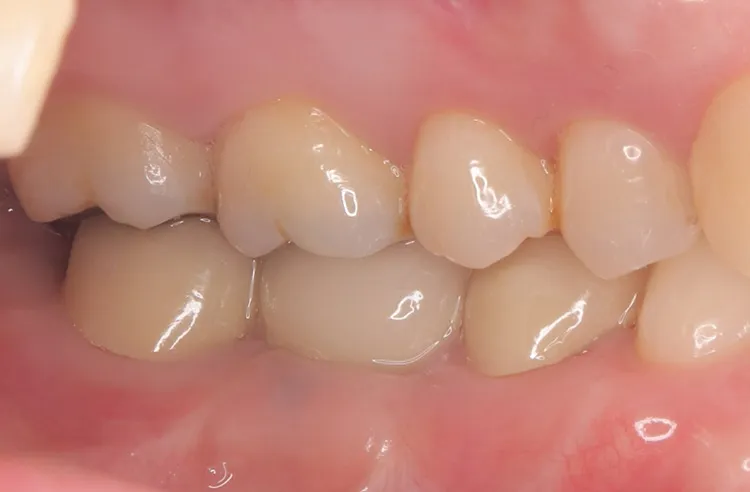

第一大臼歯1歯欠損をインプラントで回復したケースです。第一大臼歯は永久歯の中で一番最初に生える歯ですが、一番早く傷んでしまう歯でもあります。噛む力の60%を負担し噛み合わせの安定に大きく影響しますので、この歯が欠損すると噛み合わせに悪い影響を与えてしまいます。インプラントで治すことにより噛み合わせが安定するだけでなく、ブリッジのように隣在歯を削らないので天然歯の寿命を延ばすメリットもあります。

左下67 欠損に対してインプラント治療を行った症例

部分床義歯を使用していたが、どうしても慣れない上にしっかり噛むことができないためインプラント治療を希望